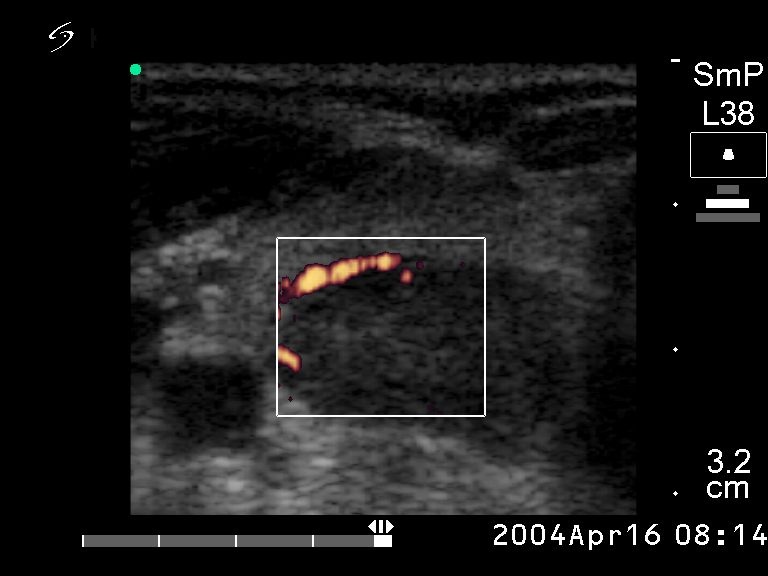

Ultrasonography: an echonormal right lobe with several small hypoechogenic lesions and a hypoechogenic nodule in the dorsal part. The nodule did not exhibit a halo sign but on Doppler mode perinodular blood flow was detected.